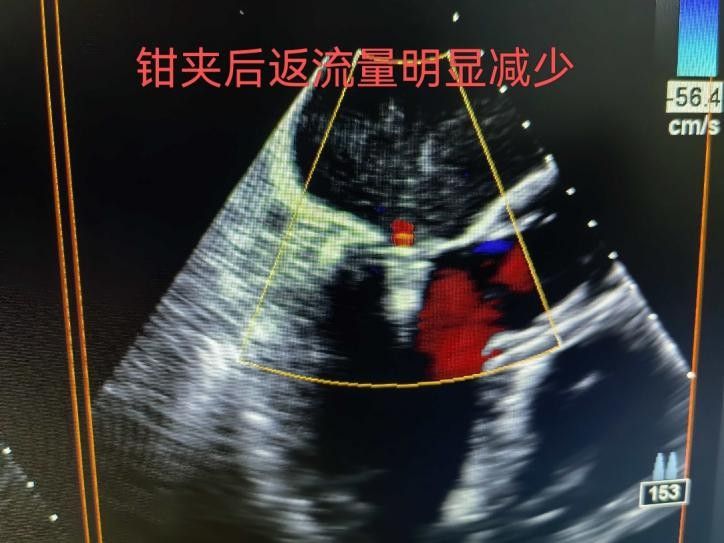

手術于11月4日下午進行,通過股靜脈穿刺送入夾合器,在食道超聲實時引導下,精準植入2枚瓣膜夾修復二尖瓣。整個過程歷時約2小時,術中出血量僅50ml。術后次日,患者即可下床活動,復查顯示EF提升至46%,二尖瓣返流面積縮小至3.0cm2,左心房縮小至66mm,胸悶、氣短癥狀明顯緩解。

2.精準定位:在食道超聲和X線引導下,將夾合器送達二尖瓣位置,通過夾合病變瓣膜減少返流;